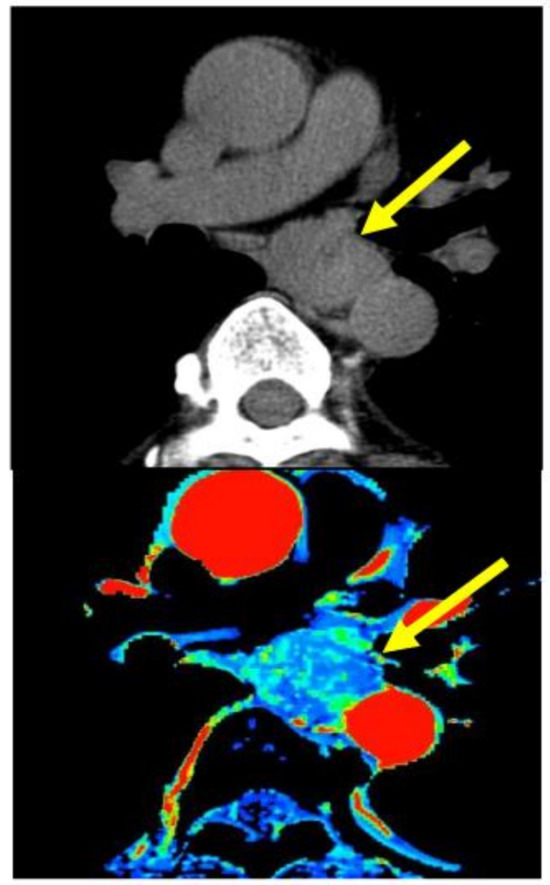

- Hayano, K.; Okazumi, S.; Shuto, K.; Matsubara, H.; Shimada, H.; Nabeya, Y. Perfusion CT can predict the response to chemoradiation therapy and survival in esophageal squamouscell carcinoma: Initial clinical results. Oncol. Rep. 2007, 18, 901–908. [Google Scholar]

- Hayano, K.; Shuto, K.; Satoh, A.; Aoyagi, T.; Narushima, K.; Gunji, H. Tumor blood flow change measured by CT perfusion during chemoradiation therapy (CRT) for monitoring response and predicting survival in patients with esophageal cancer. Esophagus 2014, 11, 72–79. [Google Scholar] [CrossRef]